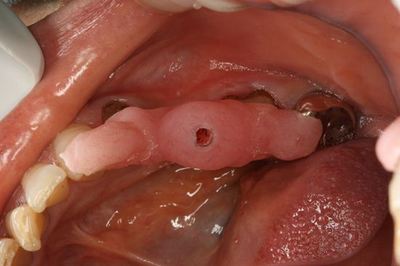

おくちの中でステントの適合を確認します。